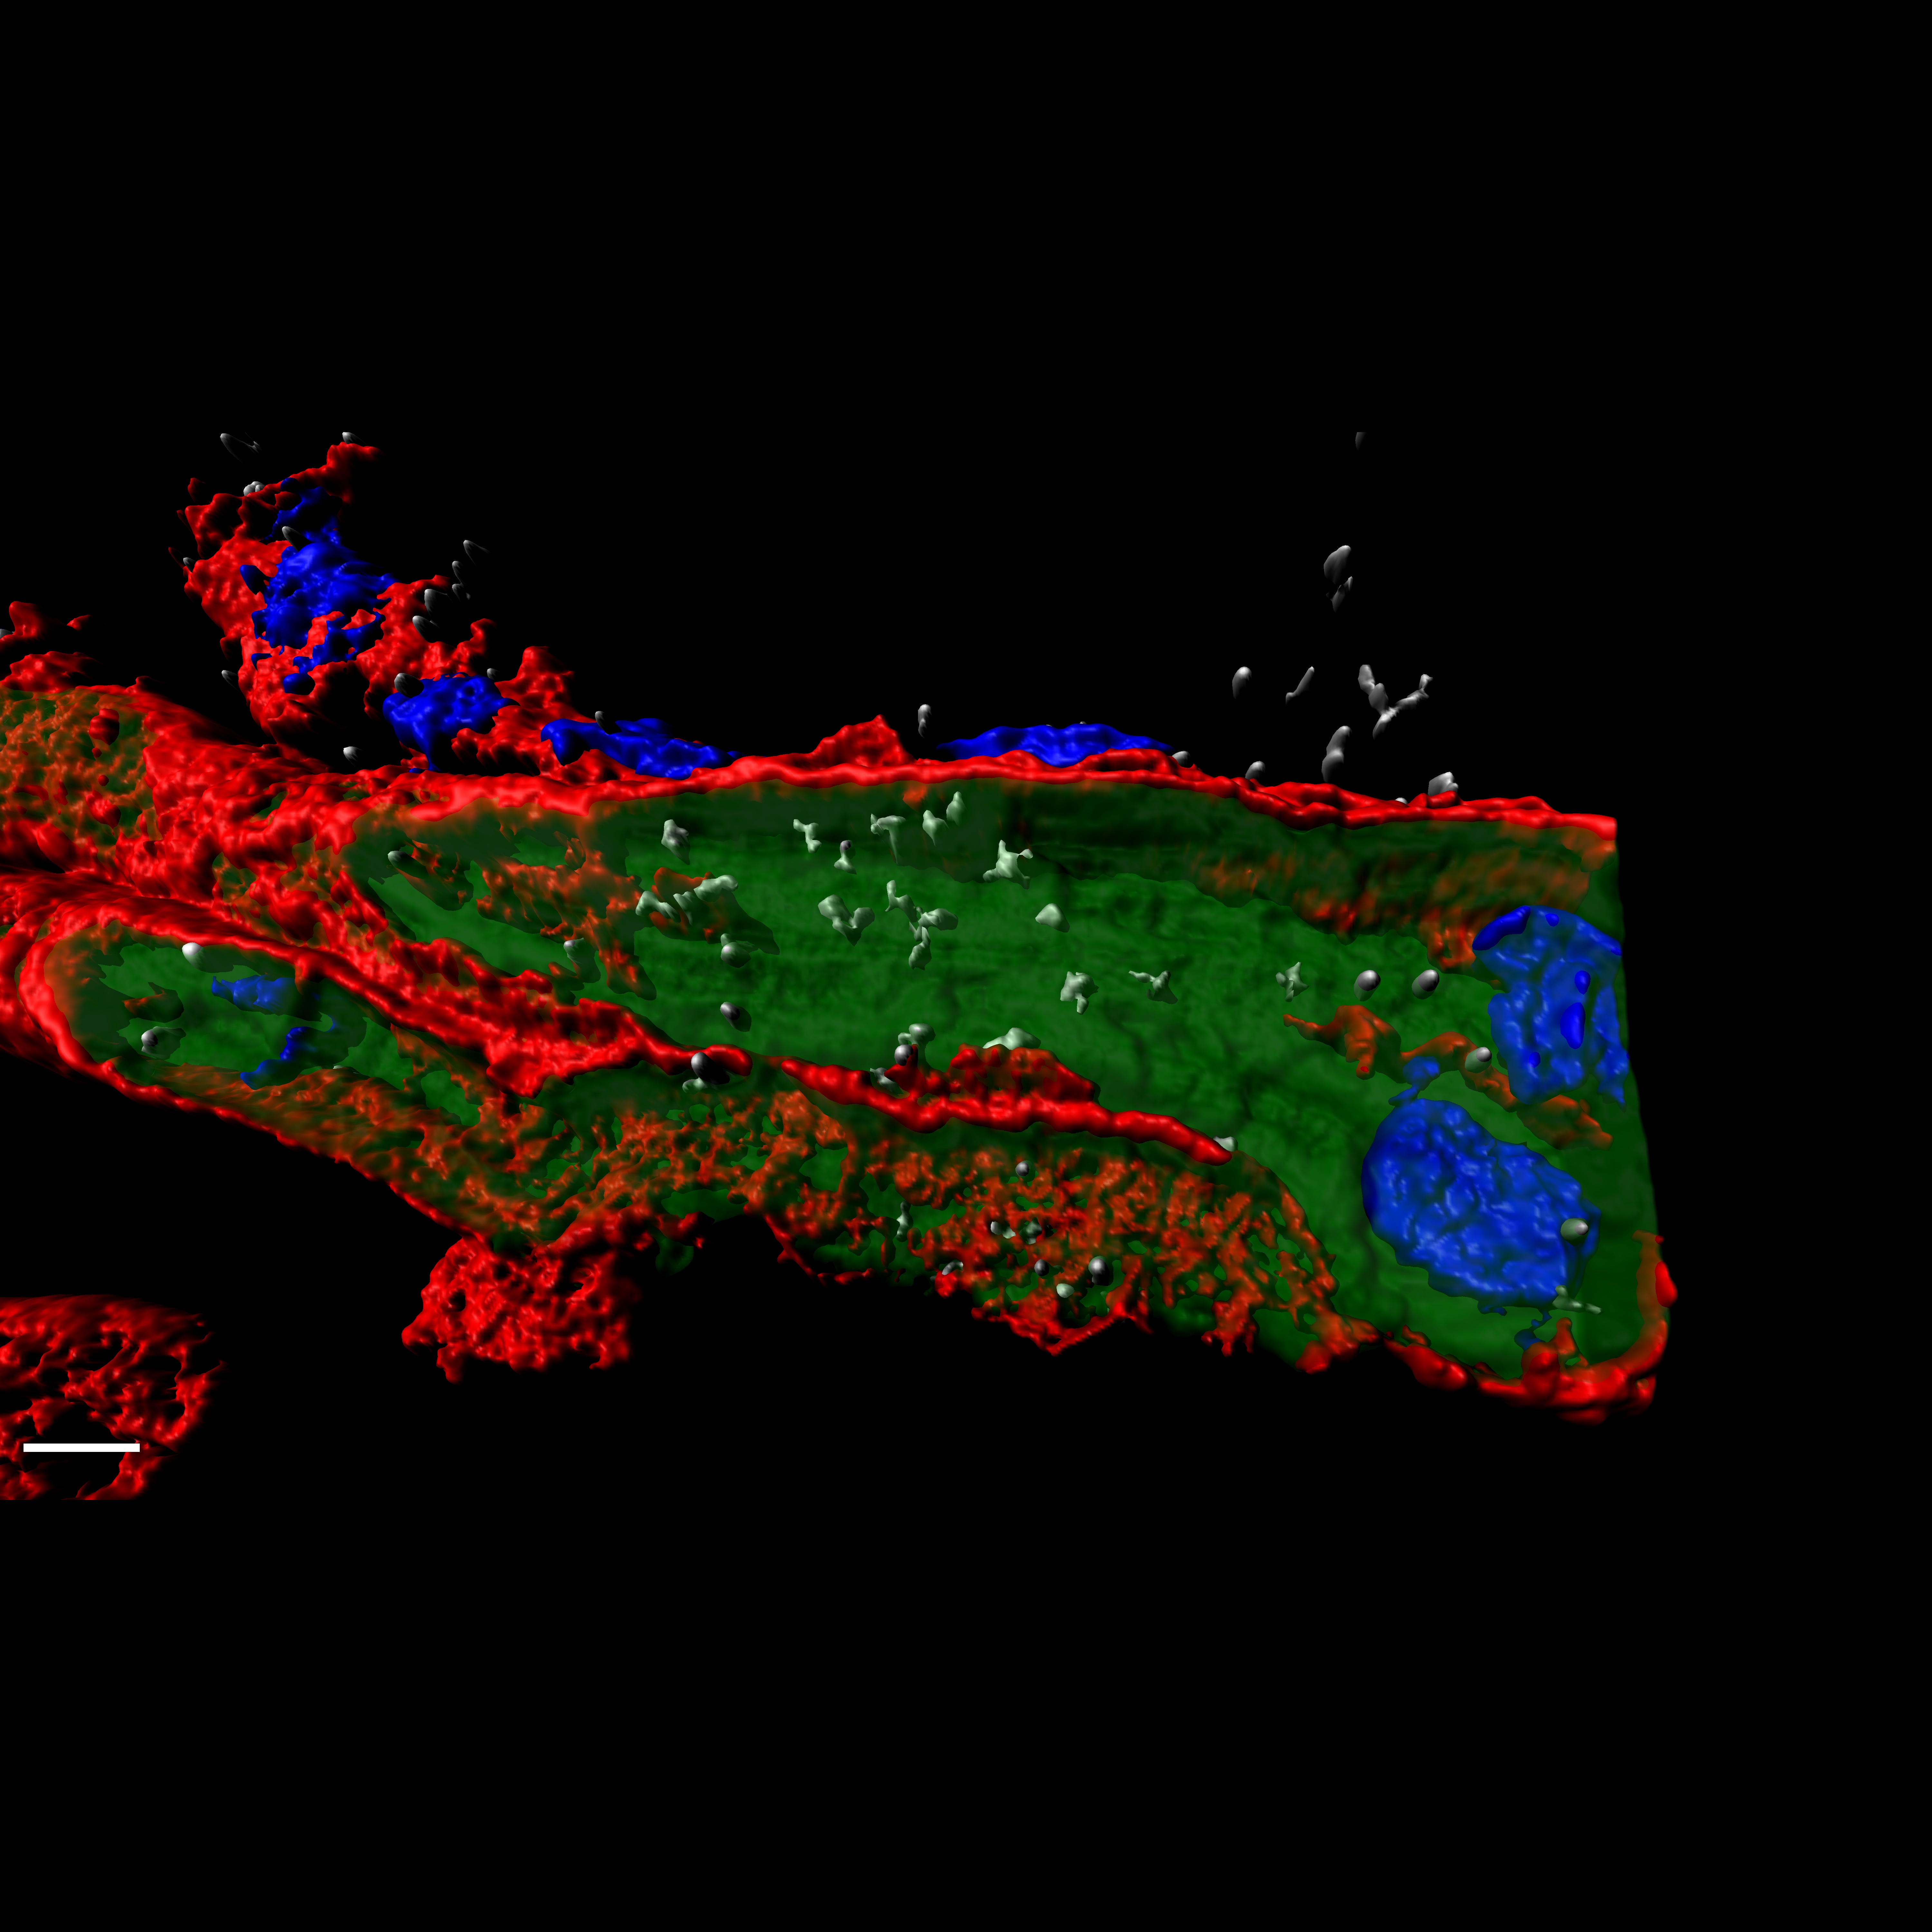

Un producto de terapias avanzadas que combina edición genómica y bioingeniería tisular, designado medicamento huérfano para la piel de mariposa